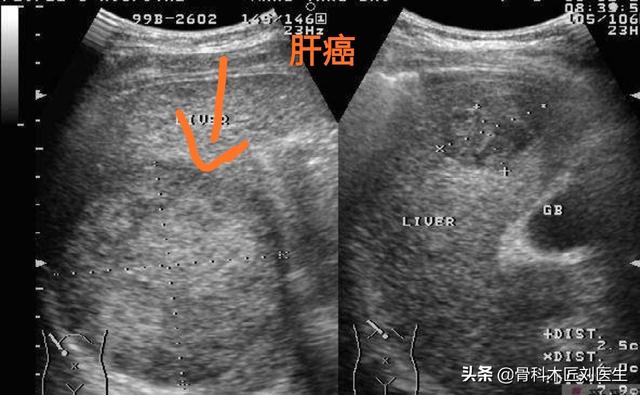

(Comme indiqué : cancer du foie métastatique)

- Tout d'abord, pour le dépistage du cancer du foie, je recommande de combiner l'échographie et l'alpha-fœtoprotéine, car l'échographie permet de détecter clairement les tumeurs hépatiques de plus d'un centimètre et l'alpha-fœtoprotéine, en tant que marqueur tumoral du cancer du foie, accroît fortement la précision du diagnostic du cancer du foie.

- Si une échographie du foie ne révèle pas de tumeur dans le foie, ou si la nature de la tumeur ne peut être déterminée, une alpha-fœtoprotéine élevée est hautement suspecte de la présence possible d'un carcinome hépatocellulaire.Une tomodensitométrie du foie peut être réalisée.Je recommanderais d'emblée une tomodensitométrie améliorée du foie, car cette technique est relativement efficace pour identifier les tumeurs hépatiques.